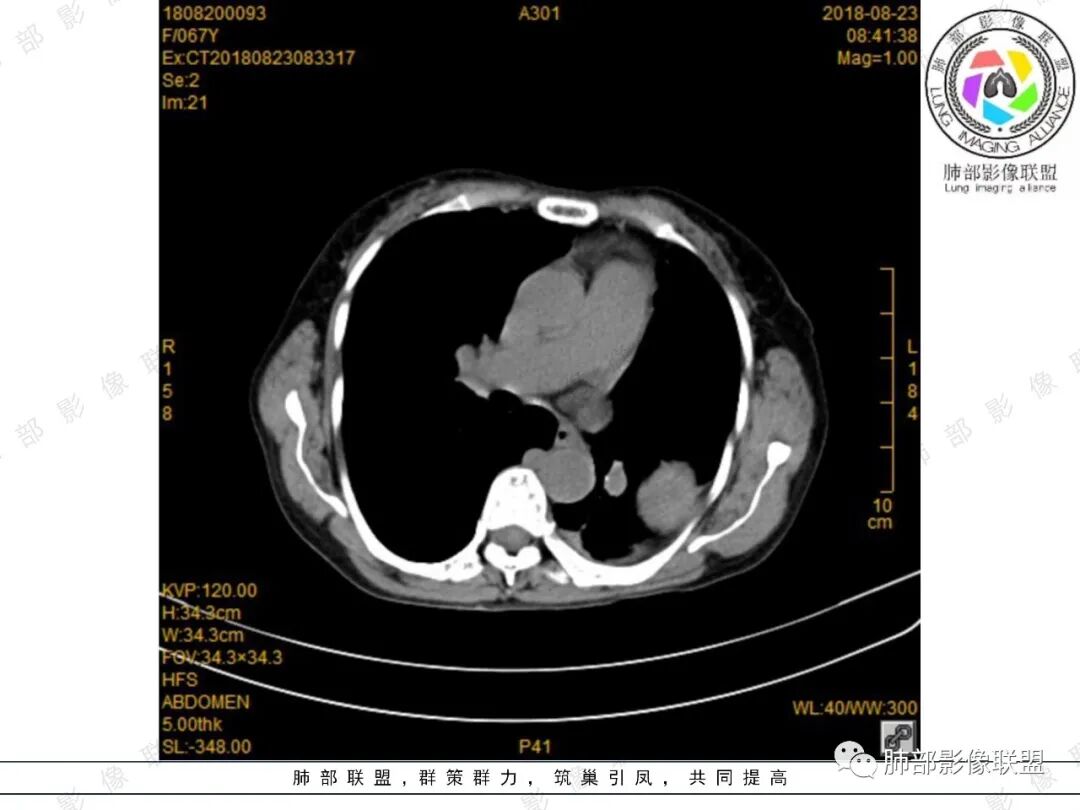

采莲:中年女性,有便血病史,左肺上叶椭圆形肿块,边缘光滑,长轴与胸膜平行,与胸膜宽基底相连,内部密度较均匀,有低密度区,密度较高,强化不明显,脊柱旁胸膜增厚,有便血病史,不知道是不是慢性,考虑来源胸膜,髓外造血?脾脏不会看。其他神经源性肿瘤?

大雄:增强确实看的有些奇怪,胸部的无强化,脾内的轻度强化。如果是EMH,按理有强化的,除非全部脂肪变性了。虽然不是EMH好发位置,但也可以。淋巴瘤强化也不符合,胸部的这个形态也不太像淋巴瘤。如果只是单纯脾大,那么孤立的EMH也很少见。

小强:脾大,延迟强化均匀,无明显占位,左胸膜下孤性增厚,局限性膨大,强化不均匀,先考虑EMH,不太支持的是临近骨质没有膨大。

看图说话:左肺肿块,边缘光滑,密度不均匀,不均匀强化,胸腔少量积液,纵隔肿大淋巴结。脾脏增大,见肿块影,不均匀强化,一元论,考虑淋巴瘤,转移瘤。

水晶石头:患者老年年女性,便血两天就诊,查NSE稍升高。胸部CT:左肺上叶类圆形肿块,边缘光滑,边界清楚,长轴与胸膜平行,与胸膜宽基底相连,内部密度较均匀,有低密度区,强化轻中度强化。综合考虑来源胸膜来源,胸膜孤立性纤维瘤可能大。鉴别其神经源性肿瘤。

月亮圆了!:左肺上叶胸膜下肿块,宽基底与胸膜相连,边缘清晰,局部肺组织受压,支气管显示不佳,平扫密度不均匀,增强后,可见轻度不均匀强化,纵隔光滑,无分叶,无毛刺,周围组织无牵拉,收缩,内部有不均匀低密度,脾脏明显肿大,脾内多发类圆形低密度影,增强后,轻度强化,有便血,考虑可能:1:淋巴瘤2:脾梗死。